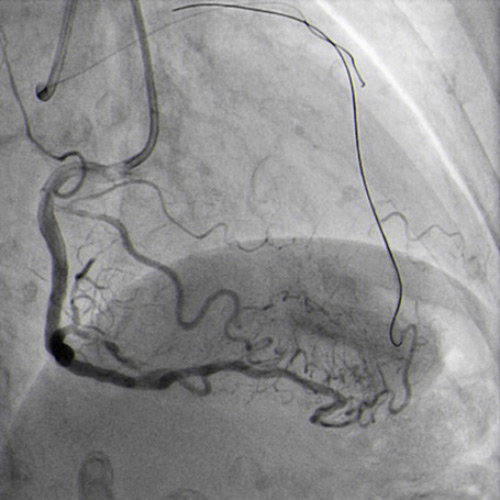

JR 4.0 guiding catheter exchanged with JL 4.0 to achieve left main (ping-pong) and position a parallel wire in left anterior descending (Figure 7.2). In the first wire we have the balloon, in the second wire a covered stent, but the perforation resolved only with balloon dilatation so we avoided, at this time to implant a covered stent.

JR 4.0 guiding catheter exchanged with JL 4.0 to achieve left main ping-pong (Figure 7.2).

After several minutes no contrast protrusion, the perforation appeared resolved, so the second wire in the JL catheter was removed and PCI completed with another DES implantation in proximal LAD (Figure 8.1).

Additional DES implanted to proximal LAD (Figure 8.1)